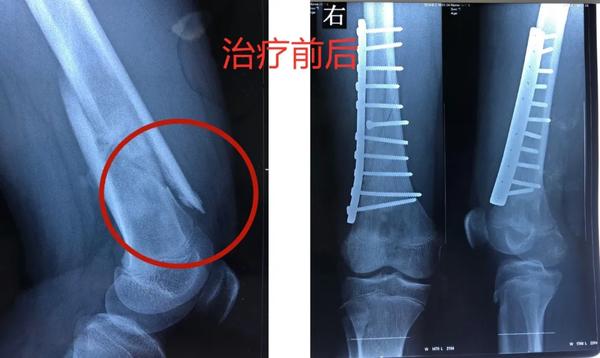

12歲的男孩兒浩浩,在學校上體育課,扭傷后突發(fā)右側(cè)大腿劇烈疼痛,不能活動,被家人緊急送到醫(yī)院,當?shù)蒯t(yī)院拍片后提示右股骨中下段斜行骨折。隨后,醫(yī)院按照一般骨折處理。

當?shù)蒯t(yī)生將病理組織送河南省腫瘤醫(yī)院病理會診,提示為骨肉瘤。消息猶如晴天霹靂,但更讓兩個孩子的父母痛苦的是,“由于按一般骨折做了手術(shù)、打了鋼板和鋼釘,破壞了腫瘤外面原本相對完整的包膜,這個自然屏障一旦被破壞,腫瘤細胞就會‘污染’周圍組織,以后想再切干凈就更困難了。”河南省腫瘤醫(yī)院骨與軟組織科主任、主任醫(yī)師姚偉濤表示。

身體異常:排除感冒、發(fā)燒引起的,患者出現(xiàn)持續(xù)發(fā)熱,并伴有體重下降,活動能力下降,且有難以解釋的持續(xù)性疼痛。骨折:腫瘤持續(xù)“破壞蠶食”骨質(zhì),最后就像浩浩和晨晨一樣,輕微的外力下就會發(fā)生一處甚至多處骨折。揪出骨肉瘤 核磁是關(guān)鍵那怎么才能確診骨肉瘤呢?檢查骨肉瘤首先要拍X片,其次是磁共振,最終要依靠活組織檢查來確診。一定不能忽視磁共振檢查。王鑫提醒道:骨肉瘤就像一個表面看起來很小的水坑,實際上坑里的水已經(jīng)向周圍浸潤了很大一片。在X光片上僅能看到很小的一個病灶,而在磁共振上,可以判斷腫瘤的實際大小和確切范圍,減少誤診漏診。就像浩浩、晨晨這樣,以為只是骨折,拍了片子,即使看出有一些異常,也可能沒在意,這樣打鋼板、鋼釘,弄破了瘤子后期治療就不好進行了。磁共振不僅對確診有幫助,而且對治療也有指導(dǎo)作用。“手術(shù)時要在腫瘤周圍正常組織內(nèi)切除腫瘤,保證腫瘤的邊界干凈,才能提高治愈效果。”王鑫解釋說。

最終,王鑫醫(yī)師組為浩浩、晨晨兩位小朋友選擇了新輔助化療,待疼痛癥狀緩解后,手術(shù)取出鋼板、鋼釘,并通過擴大切除手術(shù),完整切除長瘤子部分的股骨,并進行體外滅活,搭配腫瘤型組配人工膝關(guān)節(jié)置換,達到了既完整切除腫瘤,又保全了孩子肢體功能的目的。做到這些讓孩子遠離骨肉瘤骨肉瘤的致病原因目前并不明確,常認為是多種因素綜合導(dǎo)致,比如放射性輻射、接觸化學物質(zhì)、基因突變等。首先,家長對于孩子出現(xiàn)身體異常,一定要引起重視,發(fā)現(xiàn)子女在不明確病因的情況下出現(xiàn)了骨頭疼痛、關(guān)節(jié)腫痛,請及時前往醫(yī)院查明病因;家長要多鼓勵孩子外出進行戶外運動,不要接觸過多放射性輻射;另外,戶外運動時,也要注意關(guān)節(jié)處的保護,提醒孩子注意運動秩序和方式,避免造成骨骼損傷及軟組織拉傷。王鑫提醒,如果出現(xiàn)問題,懷疑骨腫瘤性疾病,尤其是合并病理性骨折,家長一定要帶孩子到專業(yè)的骨腫瘤科就診,必要時行磁共振檢查,仔細甄別骨折原因!